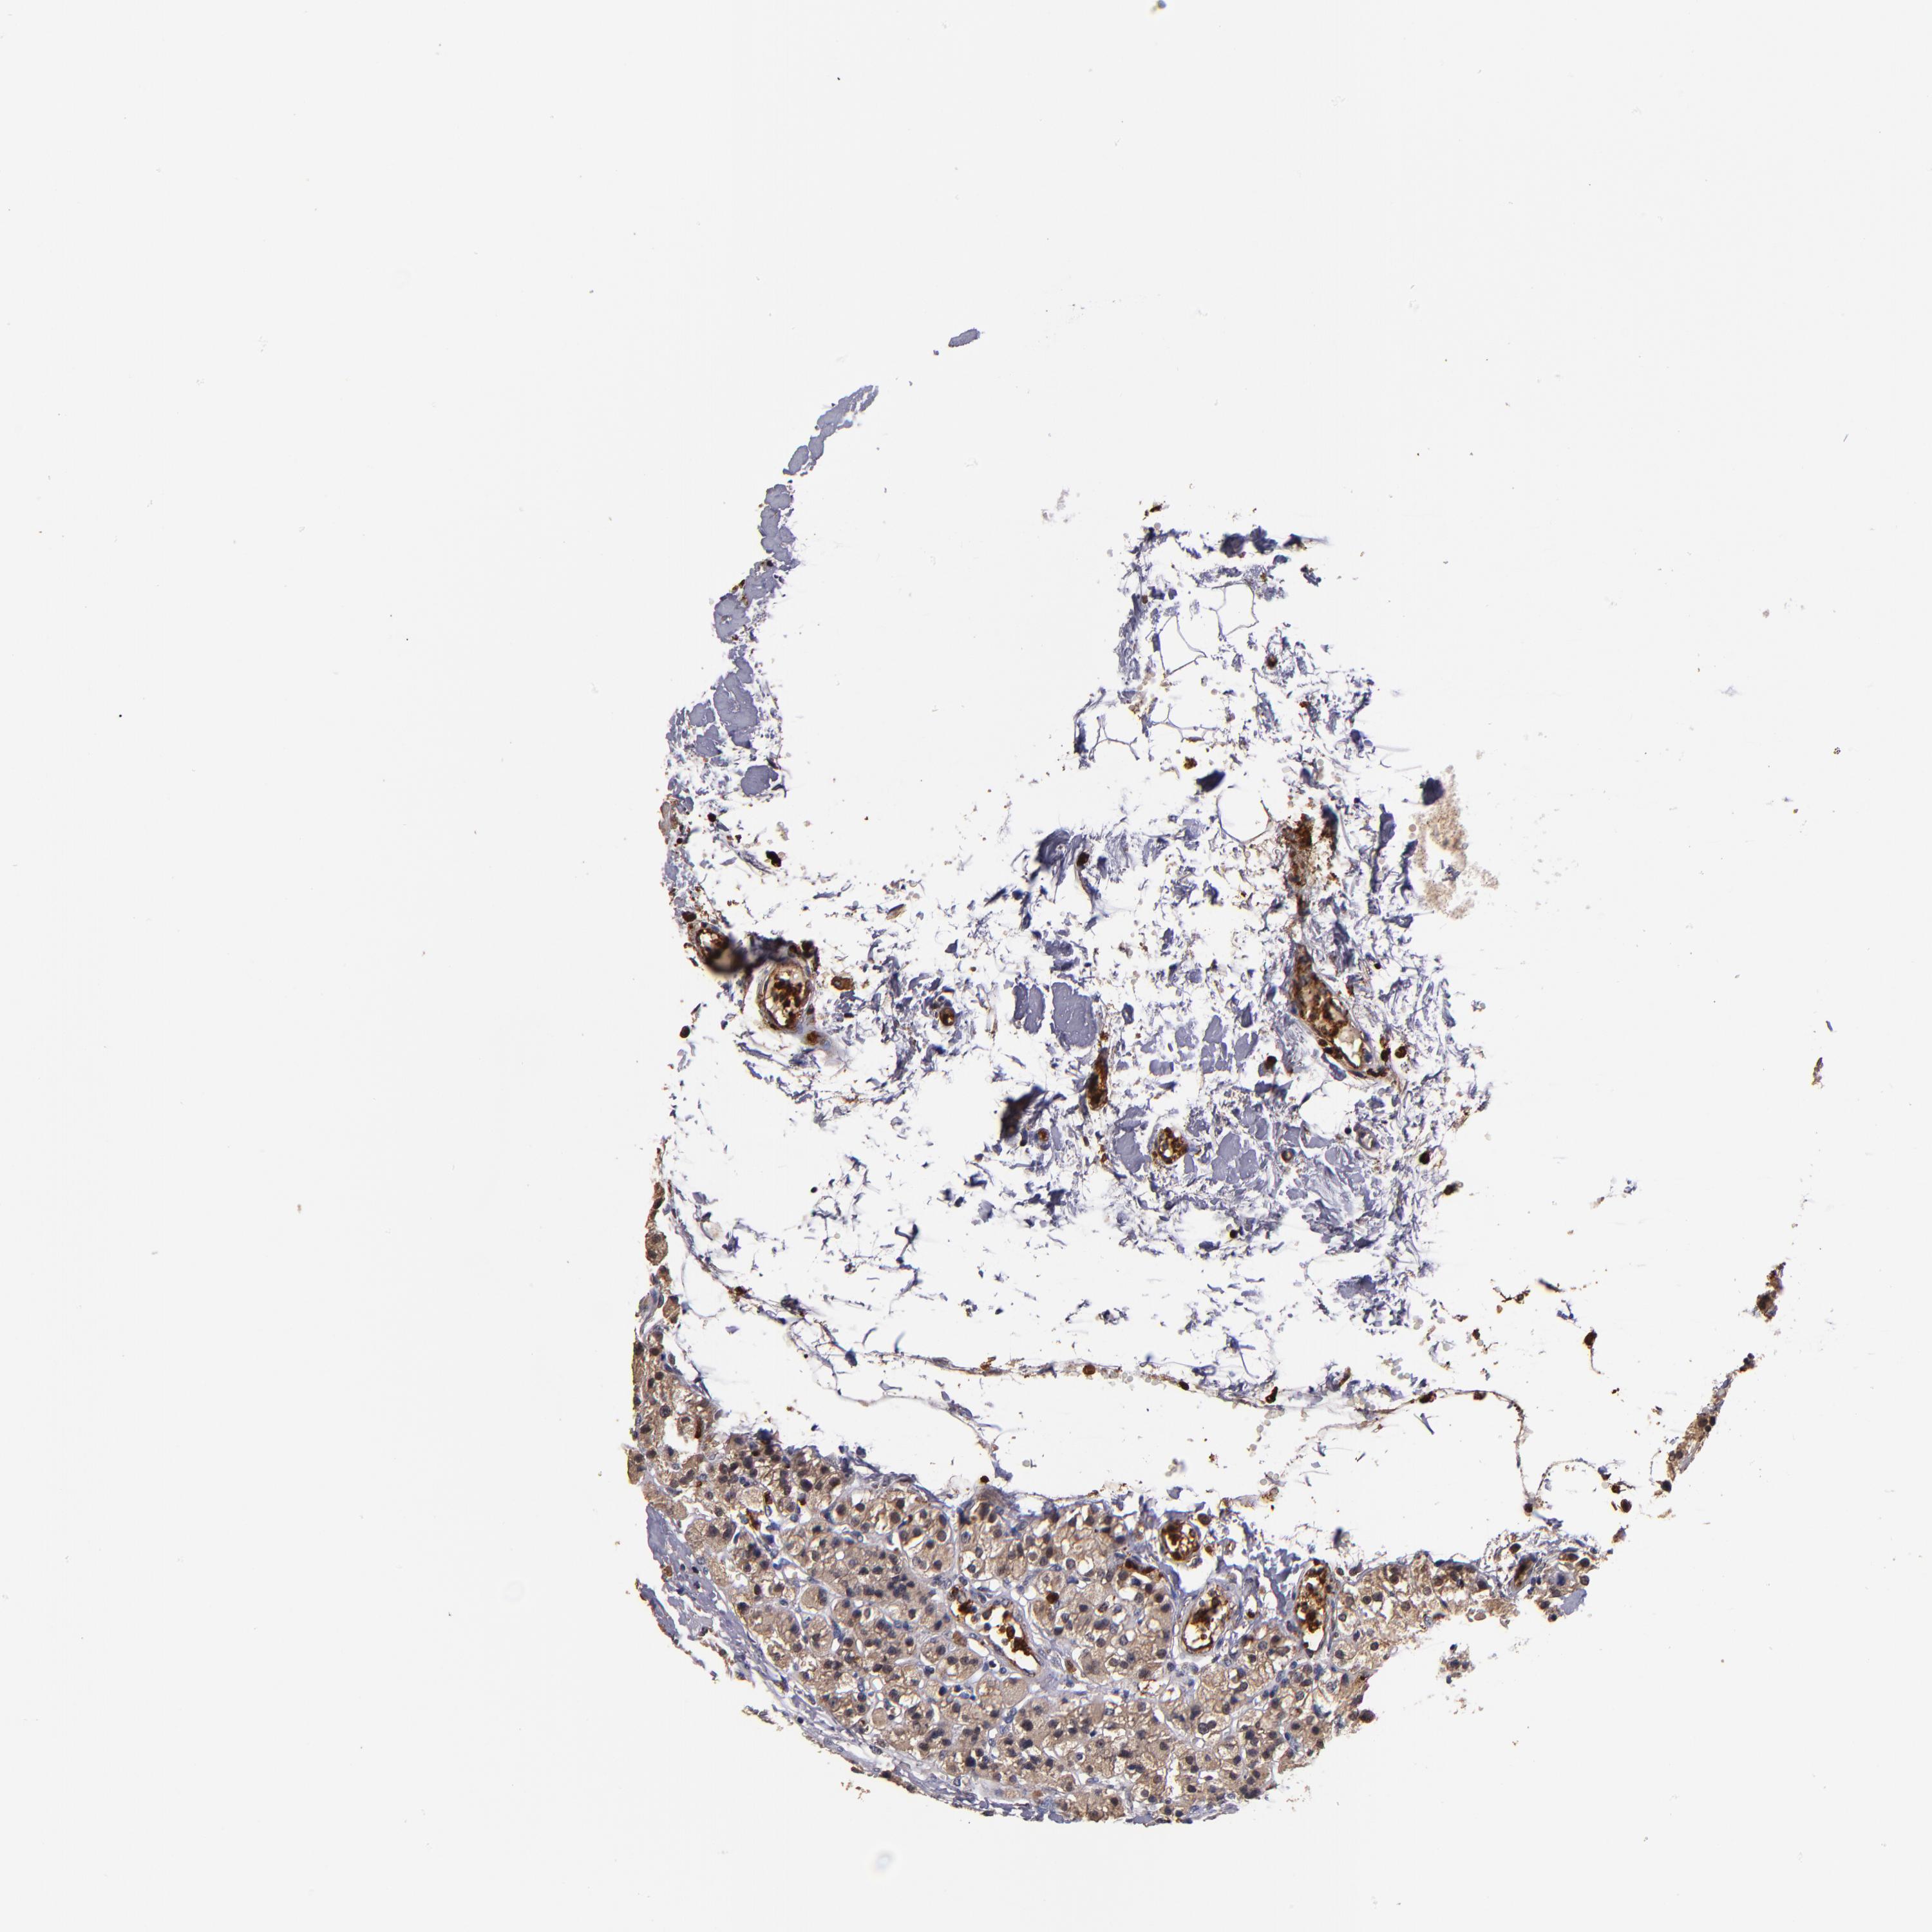

PARATHYROID GLAND - Antibody stainingi

Antibody staining in the annotated cell types in the current human tissue is reported as not detected, low, medium, or high, based on conventional immunohistochemistry profiling in selected tissues. This score is based on the combination of the staining intensity and fraction of stained cells.

Each image is clickable and will lead to virtual microscopy that enables deeper exploration of all samples and also displays staining intensity scores, fraction scores and subcellular localization as well as patient and tissue information for each sample.

Antibody HPA003054Antibody CAB046029

Glandular cells MediumNot detected